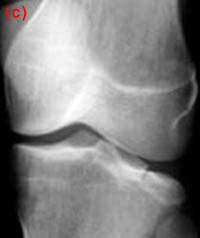

25) Name the abnormality shown in the image below.

26) How can a patellar fracture be distinguished from bipartite or multipartite patella?